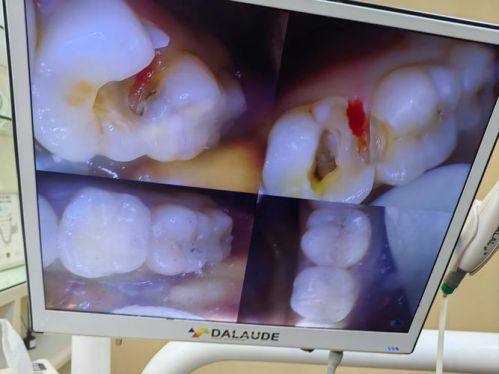

种植牙优缺点

种植牙有特别多优点。首先,它不用磨旁边的两颗牙齿,对邻牙没有损伤。其次,种植牙的寿命相对长一些,能陪伴你更长时间。在美观性和功能性方面,它比活动假牙要强特别多,也比烤瓷固定桥和全瓷桥更美观。但是种植牙也有缺点,费用略高,毕竟这是一个小手术,治疗疗程相对稍长,需要多次到医院复诊。